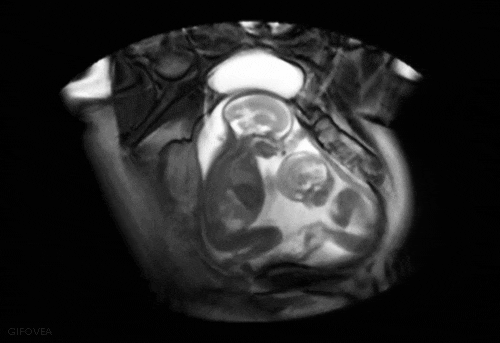

首先大家要知道,宝宝在妈妈肚子里是这样的~

是这样的....

这就是新生儿“鸟巢”式护理的依据~

新生儿“鸟巢式”护理是一种模仿子宫环境的护理方式。使胎儿在外部环境中仍然保持类似母体的卷曲姿势,为新生儿提供一个更加舒缓的过渡阶段,帮助新生儿逐渐消除脱离母体产生的紧张感,为新生儿提供安全感。